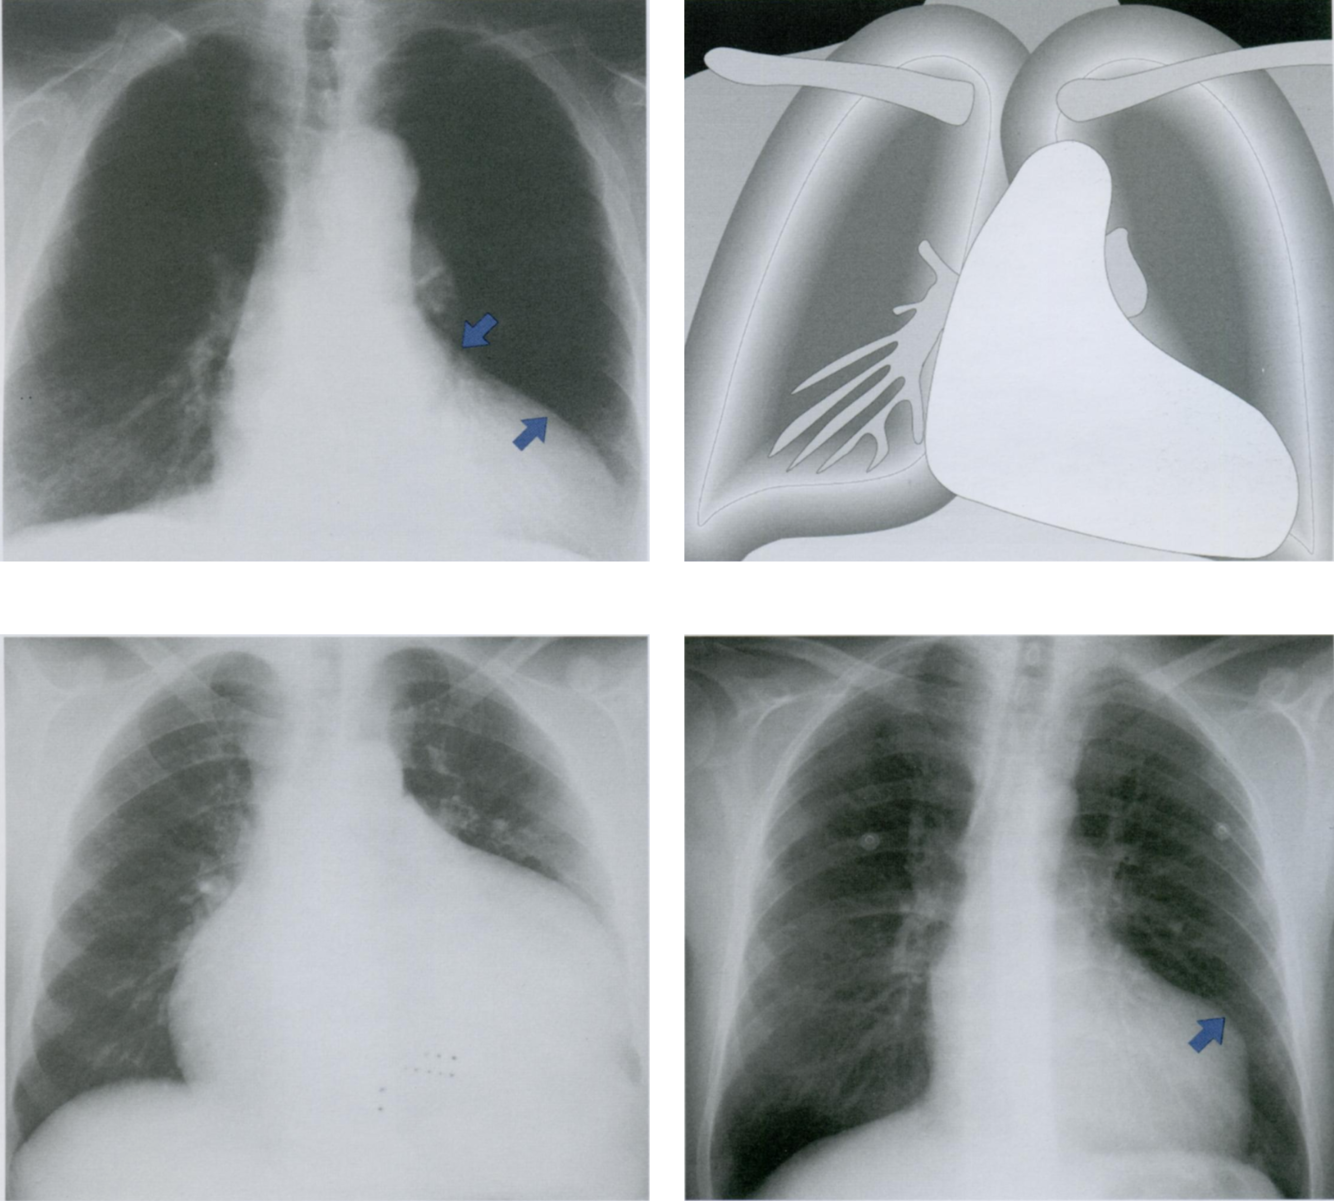

Патология аортального клапана часто формирует аортальную конфигурацию сердца на рентгенограмме грудной клетки (первый и второй снимки).

Основной механизм возникновения тот же, что и при патологии митрального клапана. Стеноз или недостаточность аортального клапана приводят к гипертрофии или дилатации левого желудочка. В результате край левого желудочка (косая стрелка вверх) смещается влево при сохранении талии сердца (косая стрелка вниз).

«Бычье сердце» (третий снимок) - термин, обозначающий крайнюю степень увеличения тени сердца в обе стороны с СГИ более 0,66. Возможными причинами являются тяжелая степень аортальной недостаточности, кардиомиопатия и сочетанные пороки сердца.

В отличие от равномерного увеличения сердечной тени при дилатации его камер (третий снимок), аневризма желудочка проявляется округлым выпячиванием (стрелка на четвертом снимке) на контуре тени сердца (четвертый снимок). В сомнительных случаях диагноз устанавливается при эхокардиографии, когда определяется парадоксальное сокращение (дискинезия) стенки левого желудочка в области аневризмы.